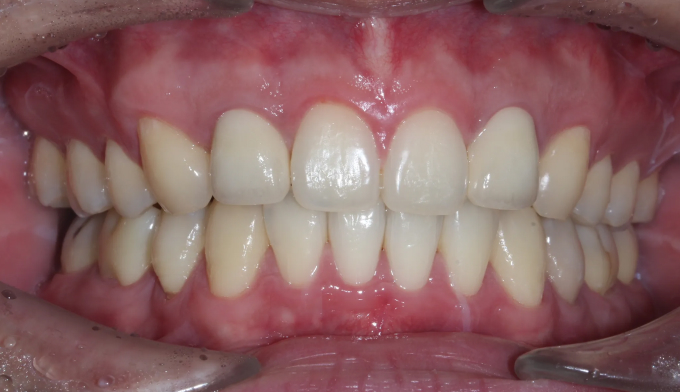

돌출감과 가지런하지 못한 앞니, 그리고 어금니의 교합이 좋지 않은 경우입니다.

좌측 아래 작은어금니가 빠진이 오래되었기 때문에, 균형을 맞추기 위해 반대편 작은어금니를 발치하여 돌출감을 해소해주었습니다. 나왔던 입이 들어가면서 턱 라인이 개선되었고, 입을 다물때도 보다 더 편안하게 되었습니다.

교정전부터 변색되어있던 양쪽 앞니는 미백과 보철치료를 동반하여 교정종료 후 개선하였습니다.

총 교정치료는 22개월입니다.